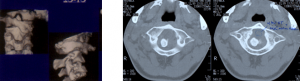

3.2.2. Chụp cắt lớp

Cho phép xác định chính xác thương tổn nghi ngờ trên X.Quang qui ước, các thương tổn xương không thấy được trên X.Quang, các mảnh xương vỡ trong ống tủy (hình 8). Với kỹ thuật tái tạo hình ảnh (Hình 9) cho phép thấy được thương tổn mỏm nha rất rõ. Ngoài ra chụp cắt lớp còn phát hiện các thương tổn phối hợp.

Hình 8. Mảnh xương trong ống tủy

Hình 9. Tái tạo hình ảnh